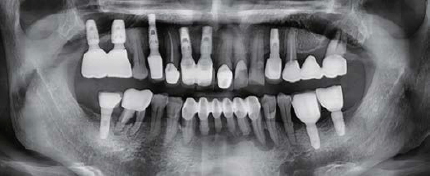

술 전 파노라마

술 후 파노라마